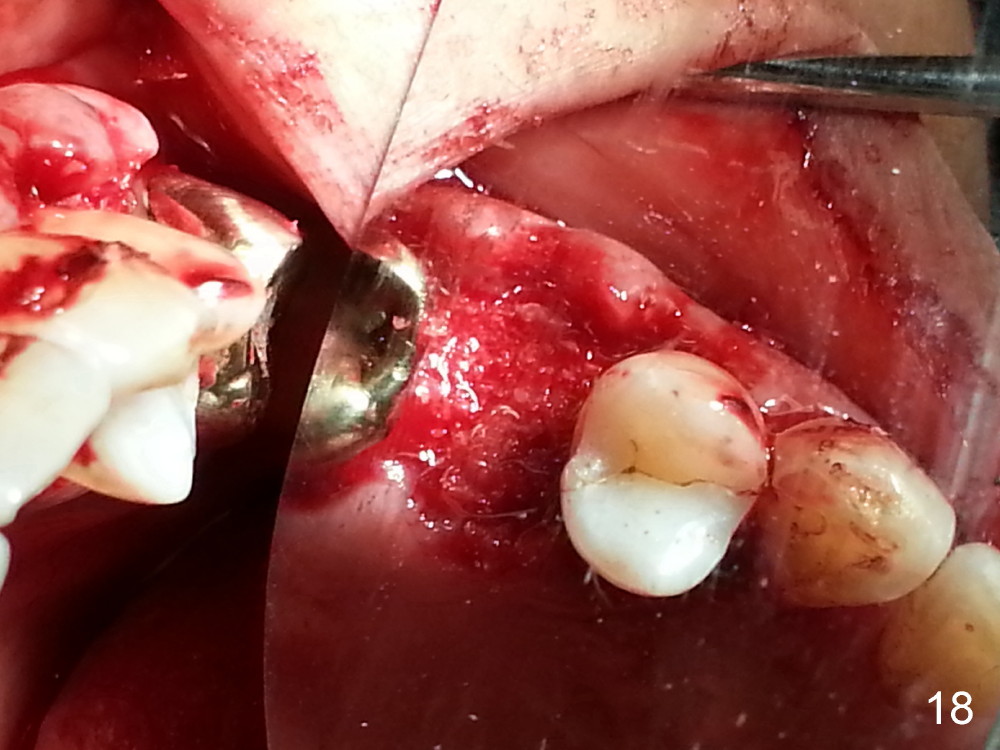

The tooth #13 appears to be affected by periodontits and occlusal trauma (Fig.1*). After using a periotome (Fig.2), the tooth is extracted (Fig.3). The buccal flap is raised (Fig.4). Gingival graft is to be harvested from the site of #15 (Fig.5). The tissue is elevated buccally (Fig.6) and separated (Fig.7). The donor site is covered by a collagen membrane (Fig.8*). A diamond bur is used to induce bleeding from the socket (Fig.9*). Osteotomy is initiated (Fig.10) and enlarged (Fig.11,12). A tapered implant is being placed (Fig.13-15) following internal sinus lift (Fig.16,17). The implant is placed subcrestally, followed by bone graft (Fig.18), soft tissue graft (Fig.19), and suturing (Fig.20 <, Fig.21).